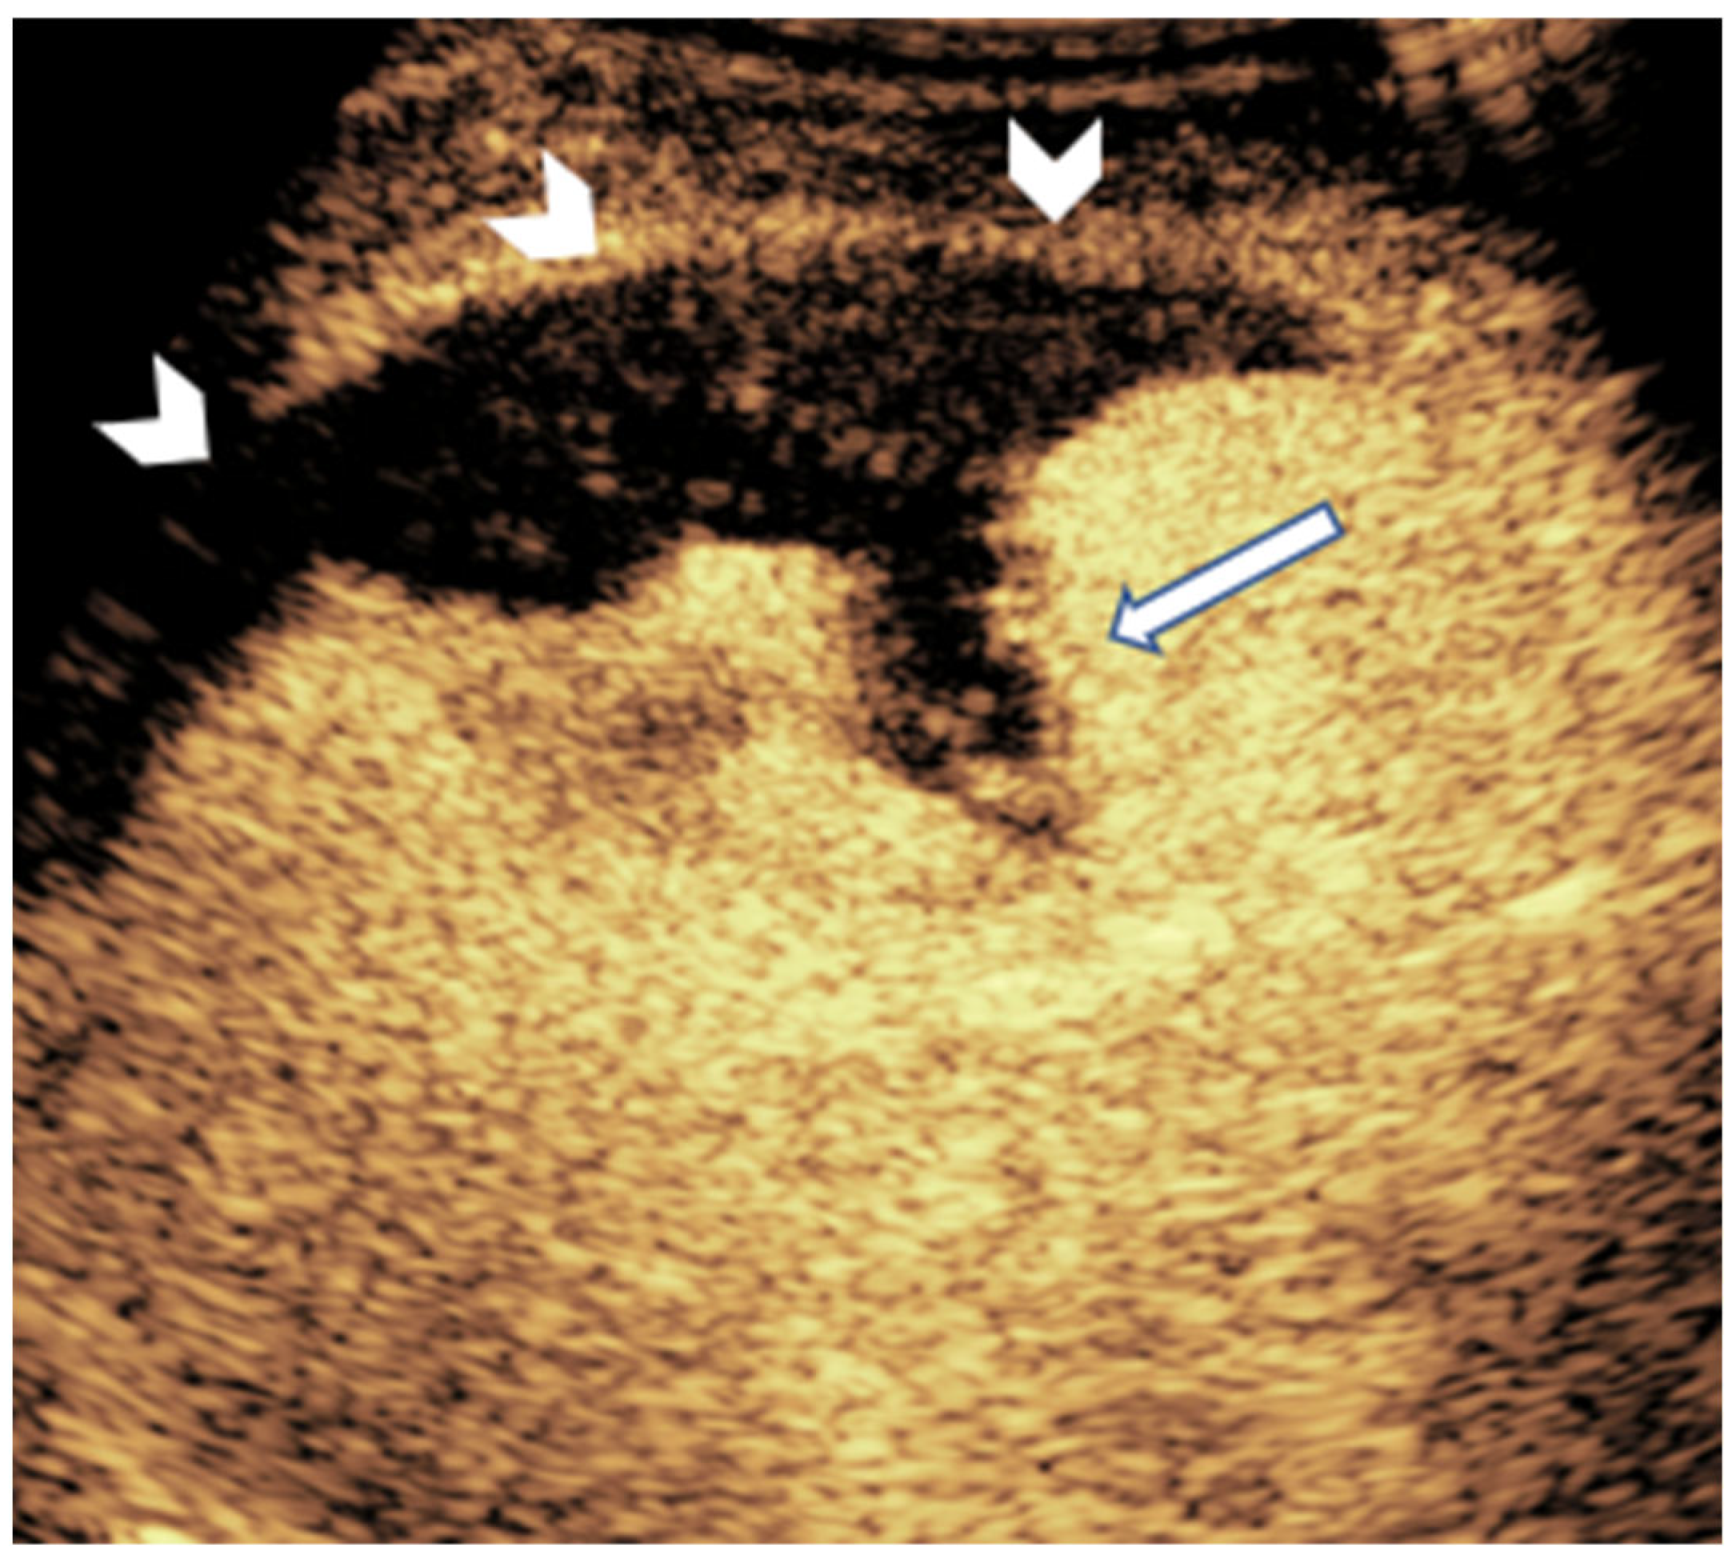

3.3. Kidney

- Zhang, W.; Yi, H.; Cai, B.; He, Y.; Huang, S.; Zhang, Y. Feasibility of contrast-enhanced ultrasonography (CEUS) in evaluating renal microvascular perfusion in pediatric patients. BMC Med. Imaging 2022, 22, 194. [Google Scholar] [CrossRef] [PubMed]

- Damasio, M.B.; Ording Müller, L.-S.; Augdal, T.A.; Avni, F.E.; Basso, L.; Bruno, C.; Darge, K.; Ključevšek, D.; Ntoulia, A.; Riccabona, M.; et al. European Society of Paediatric Radiology abdominal imaging task force: Recommendations for contrast-enhanced ultrasound and diffusion-weighted imaging in focal renal lesions in children. Pediatr. Radiol. 2020, 50, 297–304. [Google Scholar] [CrossRef]

- Riccabona, M.; Avni, F.E.; Damasio, M.B.; Ording-Müller, L.-S.; Blickman, J.G.; Darge, K.; Fotter, R.; Lee, E.Y.; Ključevšek, D.; Mentzel, H.-J.; et al. ESPR Uroradiology Task Force and ESUR Paediatric Working Group—Imaging recommendations in paediatric uroradiology, part V: Childhood cystic kidney disease, childhood renal transplantation and contrast-enhanced ultrasonography in children. Pediatr. Radiol. 2012, 42, 1275–1283. [Google Scholar] [CrossRef]

- Tufano, A.; Drudi, F.M.; Angelini, F.; Polito, E.; Martino, M.; Granata, A.; Pugliese, R.; Ricci, F.; Manenti, G.; Bonomo, L.; et al. Contrast-enhanced ultrasound (CEUS) in the evaluation of renal masses with histopathological validation—Results from a prospective single-center study. Diagnostics 2022, 12, 1209. [Google Scholar] [CrossRef] [PubMed]

- Zhu, J.; Li, N.; Zhao, P.; Wang, Y.; Song, Q.; Song, L.; Zhang, Y.; Liu, X.; Chen, H.; Wang, J.; et al. Contrast-enhanced ultrasound (CEUS) of benign and malignant renal tumors: Distinguishing CEUS features differ with tumor size. Cancer Med. 2023, 12, 2551–2559. [Google Scholar] [CrossRef]

- Sun, D.; Wei, C.; Li, Y.; Lu, Q.; Zhang, W.; Hu, B. Contrast-Enhanced Ultrasonography with Quantitative Analysis allows Differentiation of Renal Tumor Histotypes. Sci. Rep. 2016, 6, 35081. [Google Scholar] [CrossRef]

- Li, J.; Huang, X.; Wang, L.; Wang, X.; Li, Y.; Liu, X.; Zhang, H.; Chen, Y.; Zhou, Q.; Xu, T.; et al. Role of contrast-enhanced ultrasound with the enhancement pattern and qualitative analysis for differentiating hypovascular solid renal lesions. Ultrasound Med. Biol. 2024, 50, 295–303. [Google Scholar] [CrossRef] [PubMed]

- Pšeničny, E.; Glušič, M.; Pokorn, M.; Ključevšek, D. Contrast-enhanced ultrasound in detection and follow-up of focal renal infections in children. Br. J. Radiol. 2022, 95, 20220290. [Google Scholar] [CrossRef]

- Jung, H.J.; Choi, M.H.; Pai, K.S.; Kim, H.G. Diagnostic performance of contrast-enhanced ultrasound for acute pyelonephritis in children. Sci. Rep. 2020, 10, 10715. [Google Scholar] [CrossRef]